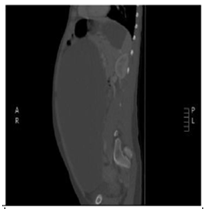

24 year old female patient who attends to overall control, at the time of referred was found asymptomatic in history but I indicated that her mother had died of liver sarcoma no other antecedent family, personal or surgical, referred menarche at 13 years, with regular menstrual cycles without recent changes from cycle frequency or amount of menstrual bleeding, condom use as a method of family planning for 6 years, when no gestational history, clinical examination only increased abdominal girth positive ascetic wave was evident, no changes in abdominal surface vasculature, masses or palpable organ enlargement were evident, no abdominal pain or discoloration of skin or mucosa, thus possible ascites was considered establish and given rise to this initial studies to study origin of ascites were requested. During the next control, no changes compared to previous clinical examination were evident in paraclinical transaminases and bilirubin. the reports in normal parameters, hematology and normal clotting times, quantitative BHCG<0.10mIU/mL (negative) and abdomen total ultrasound showed limited by the large amount of free fluid in the abdominal cavity, with decreased bilateral renal size and dilated right renal pelvis, study no proper evaluation of abdominal organs was achieved by a free liquid, the above clinical suspicion gave gynecopathologists possible neoplasic whereby extension tests were completed including abdominal tomography contrast to study possible neoplastic lesions. For the next control in clinical examinations showed a normal peripheral blood smear, differential protein and globulin normal blood, a 0.90mg/dl for CKD-EPI GFR 88.3mL/min/1.73m2, HIV testing and syphilis serology negative, alpha-fetoprotein 0.9ng/dl (negative), carcinoembryonic antigen 1.32ng/ml (negative), CA 07.16 19.9 IU/ml (negative), CA 125 8.98UI/ml (negative) and the CT abdomen which was evident great mass apparently left adnexal cystic density occupies the whole of the abdominal cavity with mass effect on abdominal organs. Figure 1 & Figure 2 with compressive effect on the right proximal ureter setting moderate hydronephrosis, Figure 3. Therefore requested assessment by the Gynecologic Oncology Service, which program for exploratory laparotomy. Day May 19, 2018 was performed in the patient exploratory laparotomy, where a large cystic mass dependent left annex of about 35cm in major diameter was found. The colour pearlescent compromising left ovary, compression and abdominopelvic displacement organs which tumor resection of the left ovary, omentectomy and appendectomy was performed, samples were sent to pathology for initial study by freezing and subsequent histopathology block. The pathology report indicated: cyst benign ovarian serous papillary cystadenoma consistent, residual ovarian parenchyma with simple epithelial follicular cysts and inclusion in the other samples not suggestive evidence for histopathological changes. Neoplasms, acute or chronic conditions; cytology extracted cyst fluid was negative for malignancy. The patient is discharged after two days without, currently present complications of surgical procedure in outpatient clinical follow by the mass of secondary ovarian origin hydronephrosis.

Figure 3 Cross section showing dilatation of the renal pelvis and right ureter.